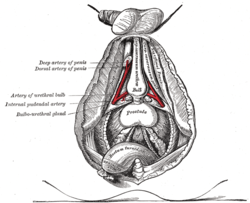

| Artery | Internal pudendal artery, inferior vesical artery, and middle rectal artery |

Male Anatomy The deeper branches of the internal pudendal artery.

The deeper branches of the internal pudendal artery. Lymphatics of the prostate.